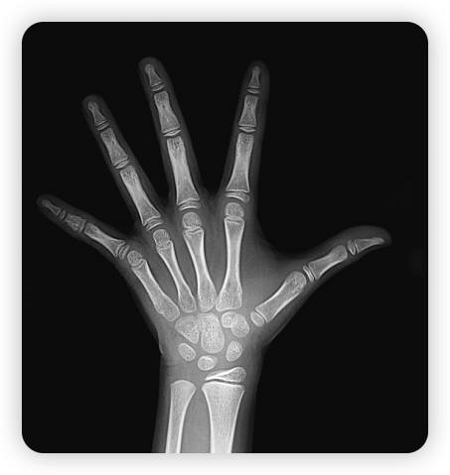

图片3

骨骺线完全闭合状态